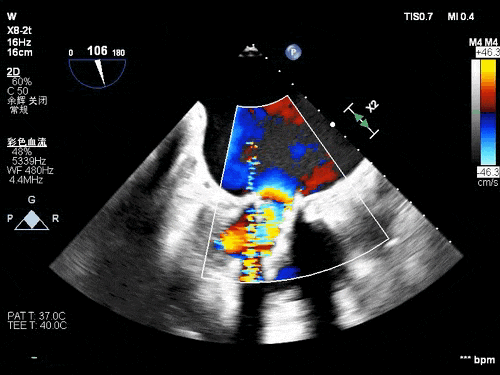

术前TEE影像

患者77岁老年女性,既往因风心病行二尖瓣生物瓣置换,入院后完善心脏超声等检查示二尖瓣生物瓣衰败并重度反流,PW测二尖前向血流速度Vmax:2.4m/s,PGmax:25mmHg。三尖瓣中度反流,心功能: 左室整体收缩功能尚好(LVEF:60%)。

术后TEE图像

瓣膜释放后超声观察无瓣周漏,峰值流速0.76m/s,峰值压差5mmHg,平均压差2mmHg,流出道峰值流速1.28m/s,峰值压差7mmHg。